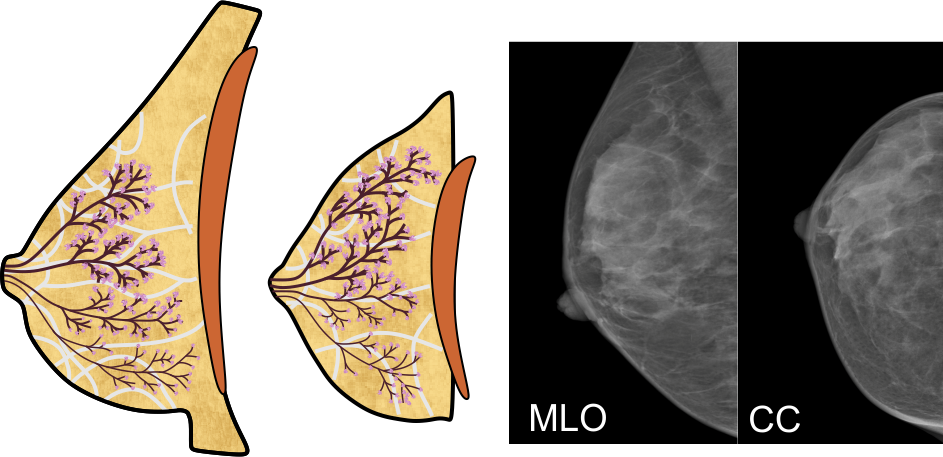

Die weibliche Brust besteht in Hauptsache aus den vier Komponenten Fettgewebe, Bindegewebe, und den Milchgängen und Milchdrüsenläppchen, die zusammen die Brustdrüse bilden:

Das Fettgewebe gibt der Brust ihre Form, das Bindegewebe durchzieht die Brust in gewölbten, fächerartigen Bahnen und verleiht ihr Stabilität. Die Milchgänge leiten die Milch zur Brustwarze, und in den Drüsenläppchen wird die Milch gebildet; die rotbraune Fläche in den obigen Abbildungen symbolisiert den Brustmuskel.

Aufbau der Brustdrüse

Die Brustdrüse gliedert sich in 10 bis 16 Drüsenlappen, im obigen Bild sind vier davon dargestellt. Ein Drüsenlappen lässt sich gut mit einem Baum vergleichen:

Der Stamm des Baums endet in der Brustwarze, seine Äste und Zweige entsprechen den Milchgängen, und die Blätter bilden die Milchdrüsenläppchen. Die 'Blätter' sind allerdings nicht flach, sondern sehen eher wie Himbeeren mit einem kurzen Stiel aus - hier eine Sicht durch das Mikroskop:

Der Stamm des Baums endet in der Brustwarze, seine Äste und Zweige entsprechen den Milchgängen, und die Blätter bilden die Milchdrüsenläppchen. Die 'Blätter' sind allerdings nicht flach, sondern sehen eher wie Himbeeren mit einem kurzen Stiel aus - hier eine Sicht durch das Mikroskop:

Mit freundlicher Genehmigung von Prof. László Tabár

Aufbau der Brust

Die vier oben genannten Gewebearten sind in ihren Anteilen in jeder Brust individuell angelegt. Die meisten Frauen haben eine ausgewogene Verteilung, bei manchen kann jedoch eine bestimmte Gewebeart überwiegen. Dazu verändert sich die Brust mit zunehmendem Alter, die Milchgänge und das Bindegewebe werden vor allem nach dem Wechsel dünner, die 'Blätter' des Baums 'verwelken' - die Drüsenläppchen schrumpfen also, und der Fettgewebeanteil wird größer. Üblicherweise entwickeln sich diese Veränderungen von innen nach außen, und von unten nach oben.

Tumore können aus allen vier Gewebearten hervorgehen. Tumore des Binde- und Fettgewebes sind zumeist gutartig, Tumore der Milchgänge und Drüsenläppchen sind meist bösartig. Diese Tumore werden üblicherweise als Brustkrebs bezeichnet.